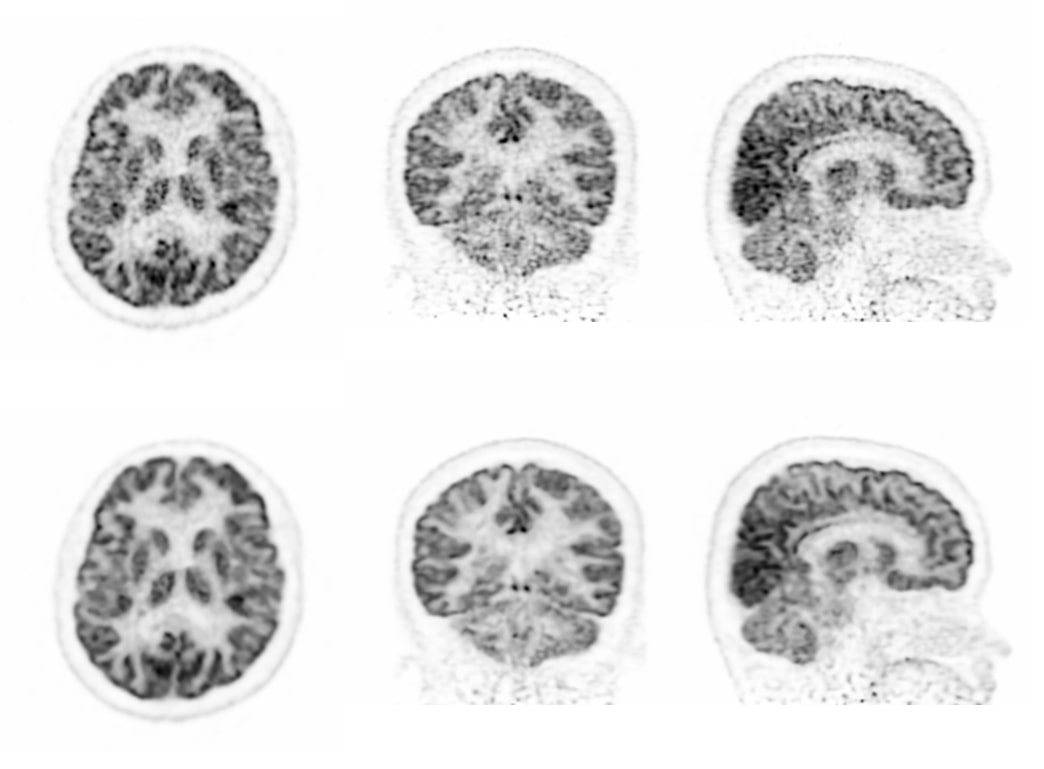

低计数图像重建

采用单事件、低能量事件等全流程数据进行全数字PET图像重建,解决低剂量、多核素等场景下高质量成像问题。

传统算法 改进的算法 双符合重建68Ga和18F混合的信号 三符合重建仅含68Ga的信号 传统算法 改进的算法 缺角度系统